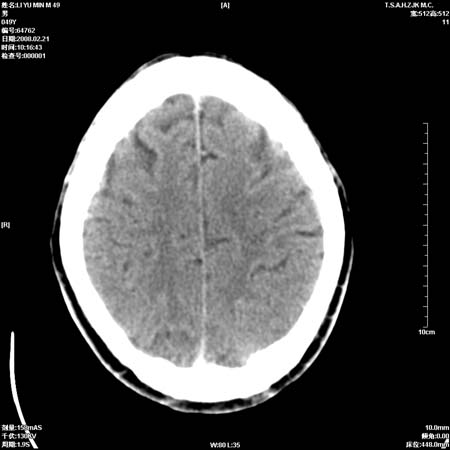

男性, 49岁, 头痛, 行ct检查后, 我科一名大夫报了蛛网膜下腔出血, 请大家讨论!

大脑纵裂池及鞍上池应该有蛛血